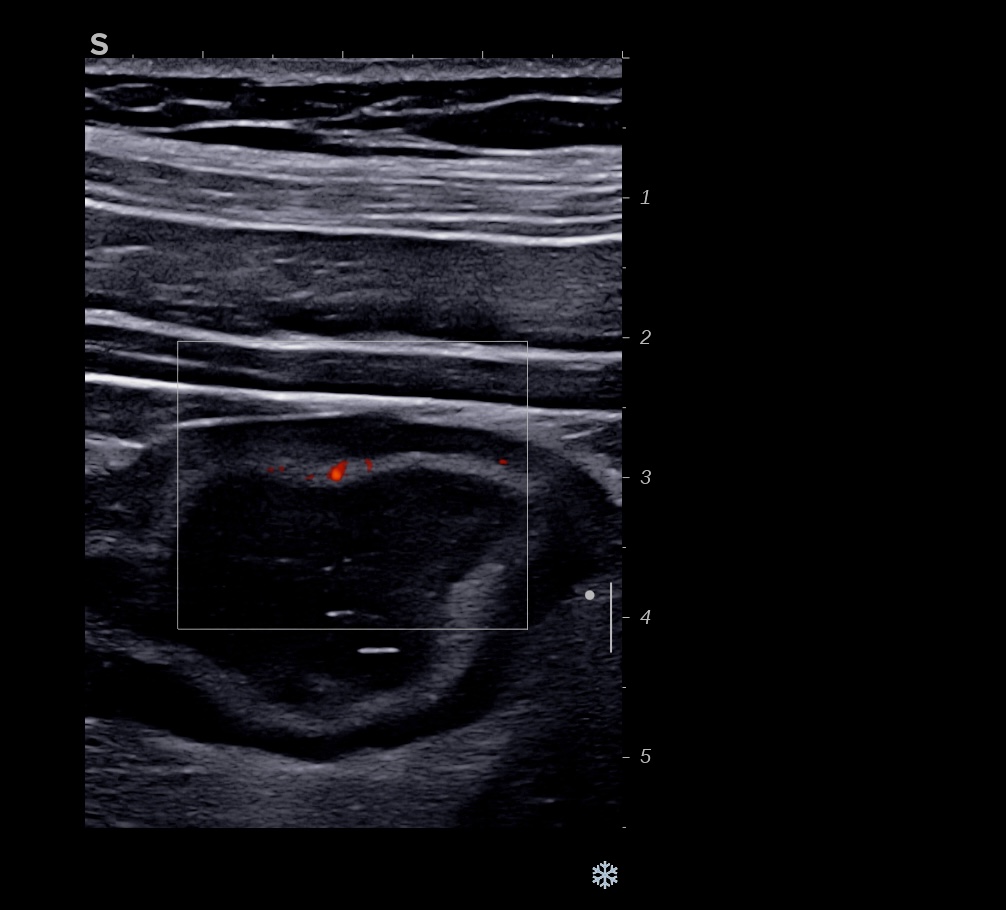

Echographie 22/12/2022

Epaississement considérable par endroit (10 ou 11 mm), disparition totale de la structure en couches, déformation de la surface avec ulcérations, déformation des contours, infiltration de la graisse, hyperactivité Doppler

Le Score de Milan (MUC) est à 17.4

Les images échographiques correspondent parfaitement aux images endoscopiques, et sont finalement beaucoup plus précises que les images scanographiques.